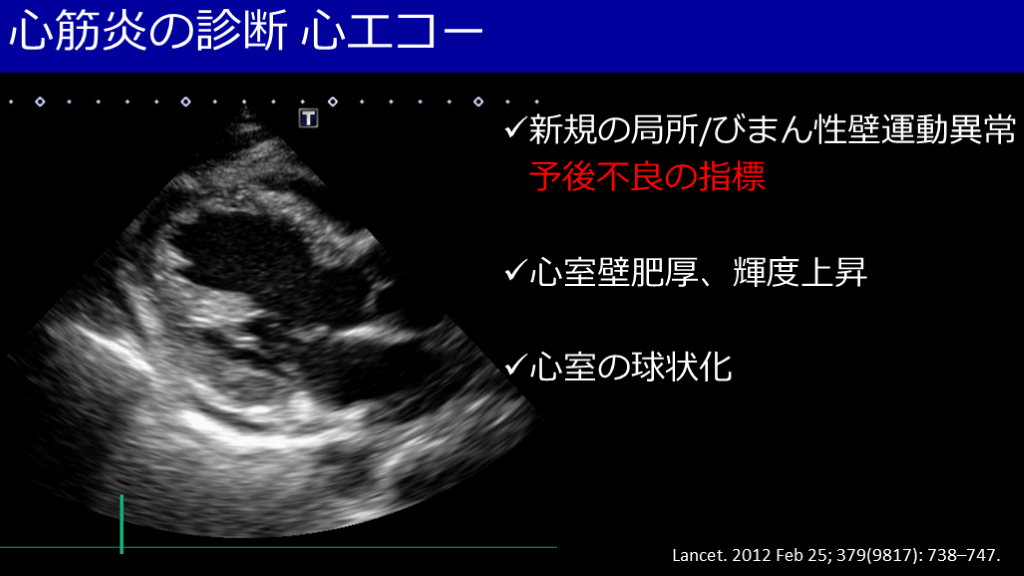

心筋炎の診断 心エコー Lancet. 2012 Feb 25; 379(9817): 738–747. 新規の局所/びまん性壁運動異常 予後不良の指標 心室壁肥厚、輝度上昇 心室の球状化